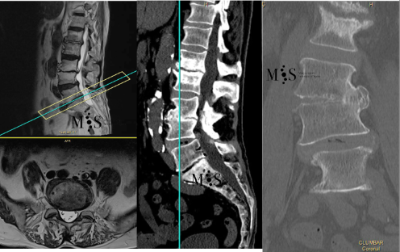

Scoliosis is a deformity/curving of the spine in the frontal plane. It can be congenital (present since birth) or degenerative (developed during the aging process). Progressive degeneration of the intervertebral disks (because of age, weight, activity, etc.) can lead to the spine to deform and curve in, ending up as a degenerative scoliosis, also called "de novo" because it is of "new" appearance in comparison to congenital scoliosis which has been present since birth.

Scoliosis lead to a curved back with the patient having problems walking with a straight back, and it can lead to an intense back pain. The spinal deformity and curving can lead to an impingement of the nerve roots which can cause radiating leg pain.

In these painful cases, surgery is indicated to (partially) correct the deformity and mainly to reduce/eliminate the pain generated by the scoliosis. In the most severe scoliosis cases an osteotomy (chiseling of a vertebral bone) may be required to straighten up the spine and reduce its deformity.

Patients who have had previous surgery on their spine and continue having pain or may even have newly appeared pain, may require revision spine surgery. Revision surgery can be challenging especially if the surgery is at the same level of the spine as a previous surgery. Scar tissue of the previously operated area makes it more difficult to differentiate anatomical planes and therefore increases the risk of damaging a nerve during surgery (due to the adherence of the nerves to the scar tissue) and infection.

On the other hand, an infection of the spine with a low-grade pathogen usually results in a chronic infection. A low-grade infection usually does not present fever but any devices previously placed in the spine (i.e. screws, rods, interbody cages, etc.) ends up loosening, generating instability and pain. Treatment of chronic infections usually requires a complete surgical removal of the infected devices, placing new devices into to stabilize the spine and a prolonged antibiotic treatment to protect the newly introduced devices from a new infection.